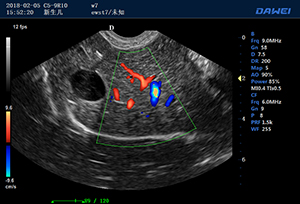

S90高端推車多普勒獸用彩超-動物寵物B超儀掃描圖 S90動物寵物B超儀檢測圖 S90多普勒獸用彩超